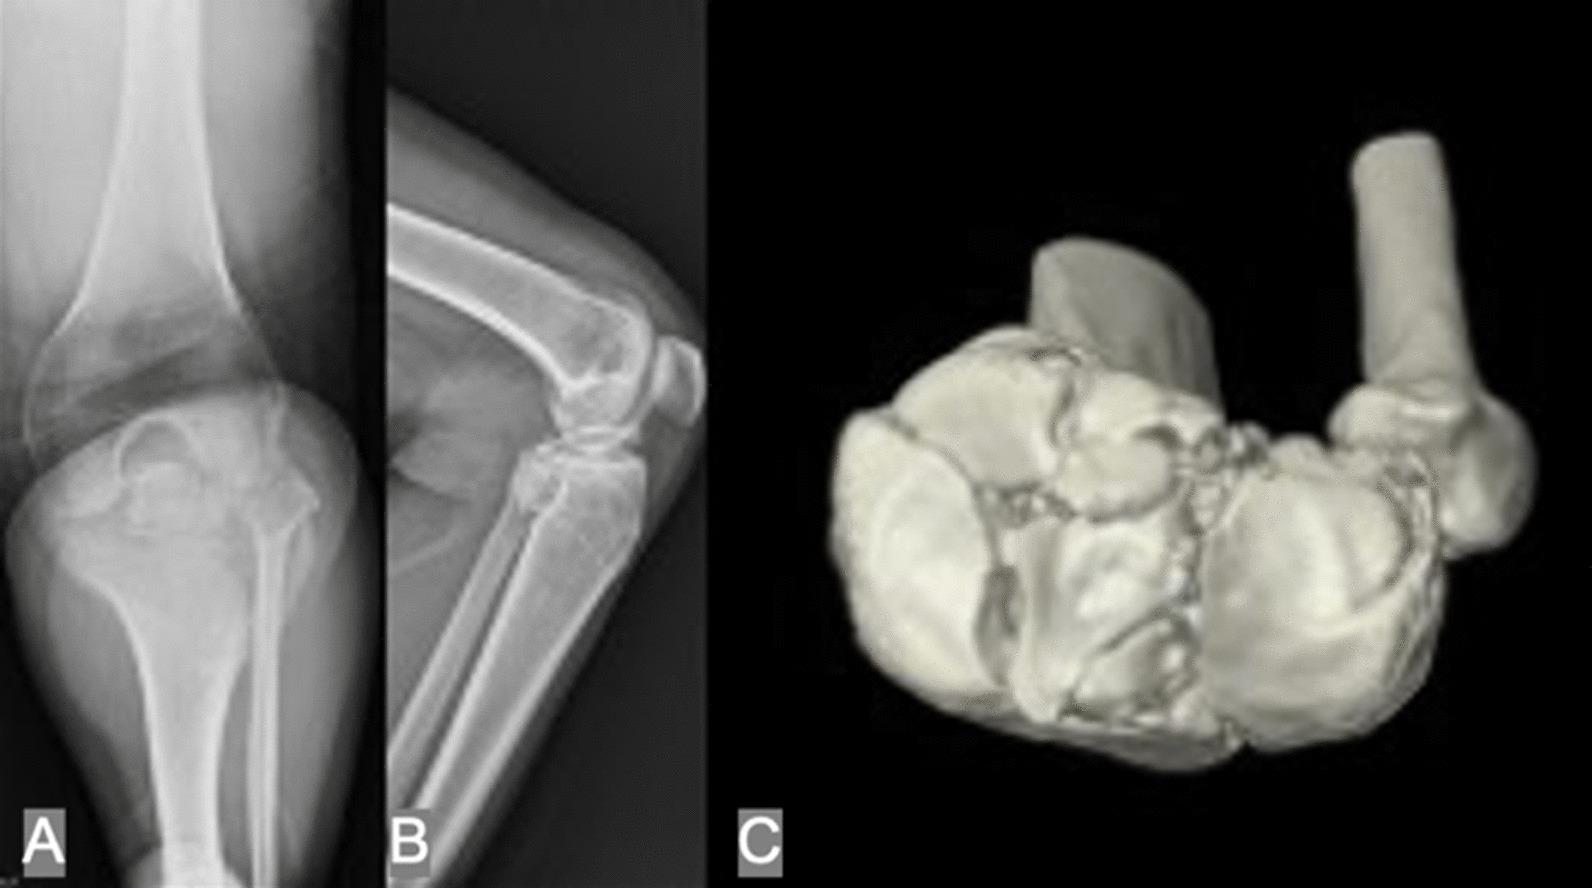

关节镜辅助复位内固定治疗复杂胫骨平台骨折:2 至 15 年随访的影像学和临床结果。

Arthroscopic-assisted reduction and internal fixation for complex tibial plateau fracture: radiographic and clinical outcomes with 2- to 15-year follow-up.

To investigate the radiologic and prognostic outcomes after using arthroscopic-assisted reduction and internal fixation (ARIF) in complex tibial plateau fractures with mid- to long-term follow-up.

This retrospective study reviewed complex tibial plateau fractures that underwent ARIF from 1999 to 2019. Radiologic outcomes, including tibial plateau angle (TPA), posterior slope angle (PSA), Kellgren-Lawrence classification and Rasmussen radiologic assessment, were measured and evaluated. The prognosis and complications were assessed by the Rasmussen clinical assessment with a minimum follow-up of 2 years.

Ninety-two consecutive patients (mean age: 46.9 years) with a mean follow-up of 74.8 months (24-180) were included in our series. Using AO classification, there were 20 type C1 fractures, 21 type C2 fractures, and 51 type C3 fractures. All the fractures achieved solid union. TPA was maintained well on average at the last follow-up and showed no significant difference compared to postoperatively (p = 0.208). In the sagittal plane, the mean PSA increased from 9.3 ± 2.9° to 9.6 ± 3.1° (p = 0.092). A statistically significant increase in PSA was also noted in the C3 group (p = 0.044). Superficial or deep infection was noted in 4 cases (4.3%), and total knee arthroplasty (TKA) was performed in 2 cases (2.2%) due to grade 4 osteoarthritis (OA). Ninety (97.8%) and 89 (96.7%) patients had good or excellent results in the Rasmussen radiologic assessment and Rasmussen clinical assessment, respectively.

The complex tibial plateau fracture could be treated successfully using arthroscopy-assisted reduction and internal fixation. Most patients achieve excellent and good clinical outcomes with low complication rates. In our experience, a higher incidence of increased slope was noted, especially in type C3 fractures. Reduction of the posterior fragment should be done cautiously during the operation.

本研究通过回顾性分析,探讨关节镜辅助复位内固定(ARIF)治疗复杂胫骨平台骨折的中、长期随访的影像学及预后结果。

本研究回顾性分析了 1999 年至 2019 年期间接受 ARIF 治疗的复杂胫骨平台骨折患者。测量和评估影像学结果,包括胫骨平台角(TPA)、后倾角(PSA)、Kellgren-Lawrence 分级和 Rasmussen 影像学评估。通过 Rasmussen 临床评估,对至少 2 年的随访结果进行预后和并发症评估。

共纳入 92 例连续患者(平均年龄 46.9 岁),平均随访时间为 74.8 个月(24-180 个月)。按 AO 分型,C1 型骨折 20 例,C2 型骨折 21 例,C3 型骨折 51 例。所有骨折均达到骨性愈合。最后一次随访时 TPA 平均保持良好,与术后相比无显著差异(p=0.208)。在矢状面,平均 PSA 从 9.3±2.9°增加到 9.6±3.1°(p=0.092)。C3 组 PSA 也有显著增加(p=0.044)。4 例(4.3%)发生浅表或深部感染,2 例(2.2%)因 4 级骨关节炎(OA)行全膝关节置换术(TKA)。Rasmussen 影像学评估和 Rasmussen 临床评估中,90(97.8%)和 89(96.7%)例患者结果为良好或优秀。

关节镜辅助复位内固定治疗复杂胫骨平台骨折可获得满意疗效。大多数患者并发症发生率低,临床结果良好或优秀。我们的经验表明,术后后倾角增加的发生率较高,尤其是 C3 型骨折。手术中应谨慎复位后关节面。